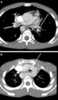

Absent main pulmonary artery